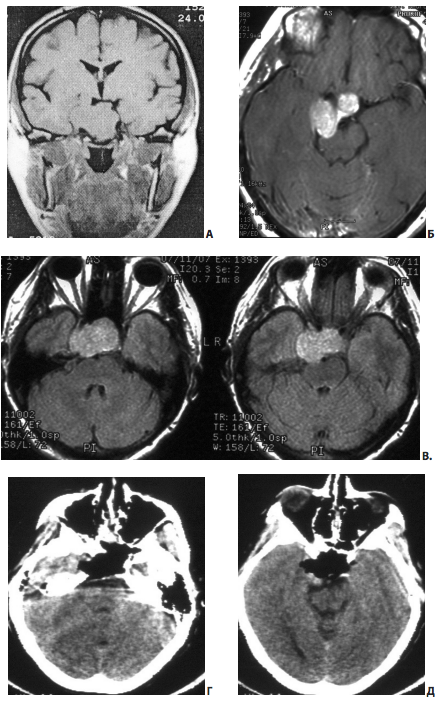

Радикальное удаление порции опухоли, расположенной латеральнее сонной артерии (в тех случаях, когда артерия обращена аденомой со всех сторон, рис. 15) возможно далеко не всегда; в большей степени это относится к части аденомы, расположенной в передних отделах кавернозного синуса (особенно в передне-нижних).

Рис. 15. Пример субтотального удаления эндо-супра-латероселлярной соматотропиномы: А — МРТ до операции; Б — интраоперационное фото (30; эндоскоп) — сонная артерия в полости кавернозного синуса обращена опухолью со всех сторон; В — МРТ после операции; после операции уровень СТГ в норме, но латеральнее ВСА — остаток опухоли

Достаточно успешное удаление опухоли из задне-верхних и задне-нижних отделов кавернозного синуса достигается заметно чаще даже при выраженной инвазии аденомы в полость синуса. Удаление опухоли при умеренной инвазии опухоли (когда опухоль обрастает лишь медиальную стенку внутренней сонной артерии, см. рис. 16) в полость синуса, также обычно не составляет значительной сложности.

Рис. 16. Этап удаления опухоли из полости кавернозного синуса. Удаление опухоли при умеренной инвазии аденомы в кавернозный синус (опухоль обрастает лишь медиальную часть сонной артерии): 1 — сонная артерия; 2 — латеральная стенка кавернозного синуса; 3 — отсос